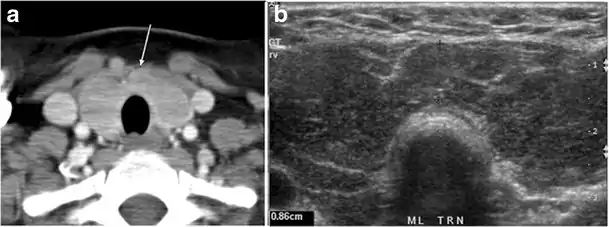

Intra-thyroid parathyroid adenoma

Parathyroid adenoma (PA) is the most common cause of primary hyperparathyroidism. Ectopic parathyroid adenoma is rare. The third and fourth pharyngeal pouches represent the embryological origin of the parathyroid tissues, and ectopic parathyroid adenoma can ultimately develop anywhere along their migration course. In a large retrospective study of patients with primary hyperparathyroidism, PA was detected in the intra-thyroid location in 0.7% of cases. In another retrospective analysis of 202 patients with ectopic PA, the intra-thyroidal location was found in 18% of the cases. Intra-thyroid parathyroid adenomas mimic thyroid nodules in CT scans and may even show uptake on a thyroid iodine scan. Correlation with laboratory workup, including measurement of serum parathyroid hormone and calcium level, is required. In addition, the evaluating radiologist should search for radiological manifestations of hyperparathyroidism, such as osteopenia, bone resorption, and brown tumours (Fig. 22).[1]

Fig. 22. A 26-year-old male patient with elevated serum parathyroid hormones and calcium secondary to intra-thyroid parathyroid adenoma. a, b Enhanced axial and coronal CT scan of the neck demonstrate a well-defined hypodense right thyroid nodule (white arrows). c Bone window coronal CT scan shows lytic expansile lesions at the right mandible and left frontal bone (white arrows). d Transverse colour Doppler ultrasound of the neck demonstrates a well-defined, heterogonous, predominantly hypoechoic right thyroid nodule measuring 2.7 cm, with mild increased vascularity and no internal micro-calcifications (white arrow). e, f Delayed anterior planar and fused SPECT/CT parathyroid Sestamibi scan at 2 hours demonstrate persistent focal activity in the right thyroid lobe (white arrows). Note the scattered mandibular/maxillary uptakes in planar image representing the known brown tumours.[1]

In the case of inconclusive Tc99m Sestamibi and neck US imaging, FNA biopsy with FNA-iPTH (intact parathyroid hormone) measurement can provide simultaneous biochemical and cytological evidence. Elevated FNA-iPTH measurement, as compared to serum iPTH, is considered positive and diagnostic of parathyroid adenoma.[1]